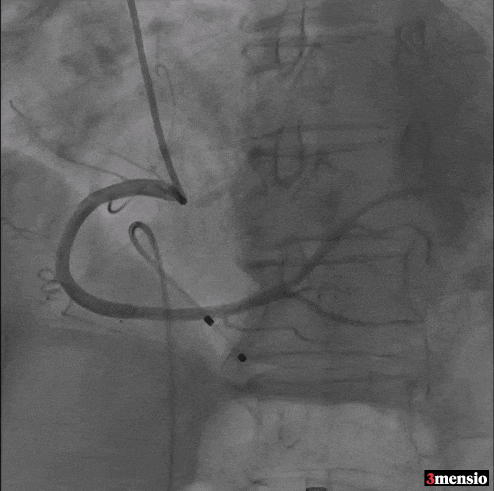

Step 2 瓣膜定位、释放

Step 3 瓣膜释放后造影